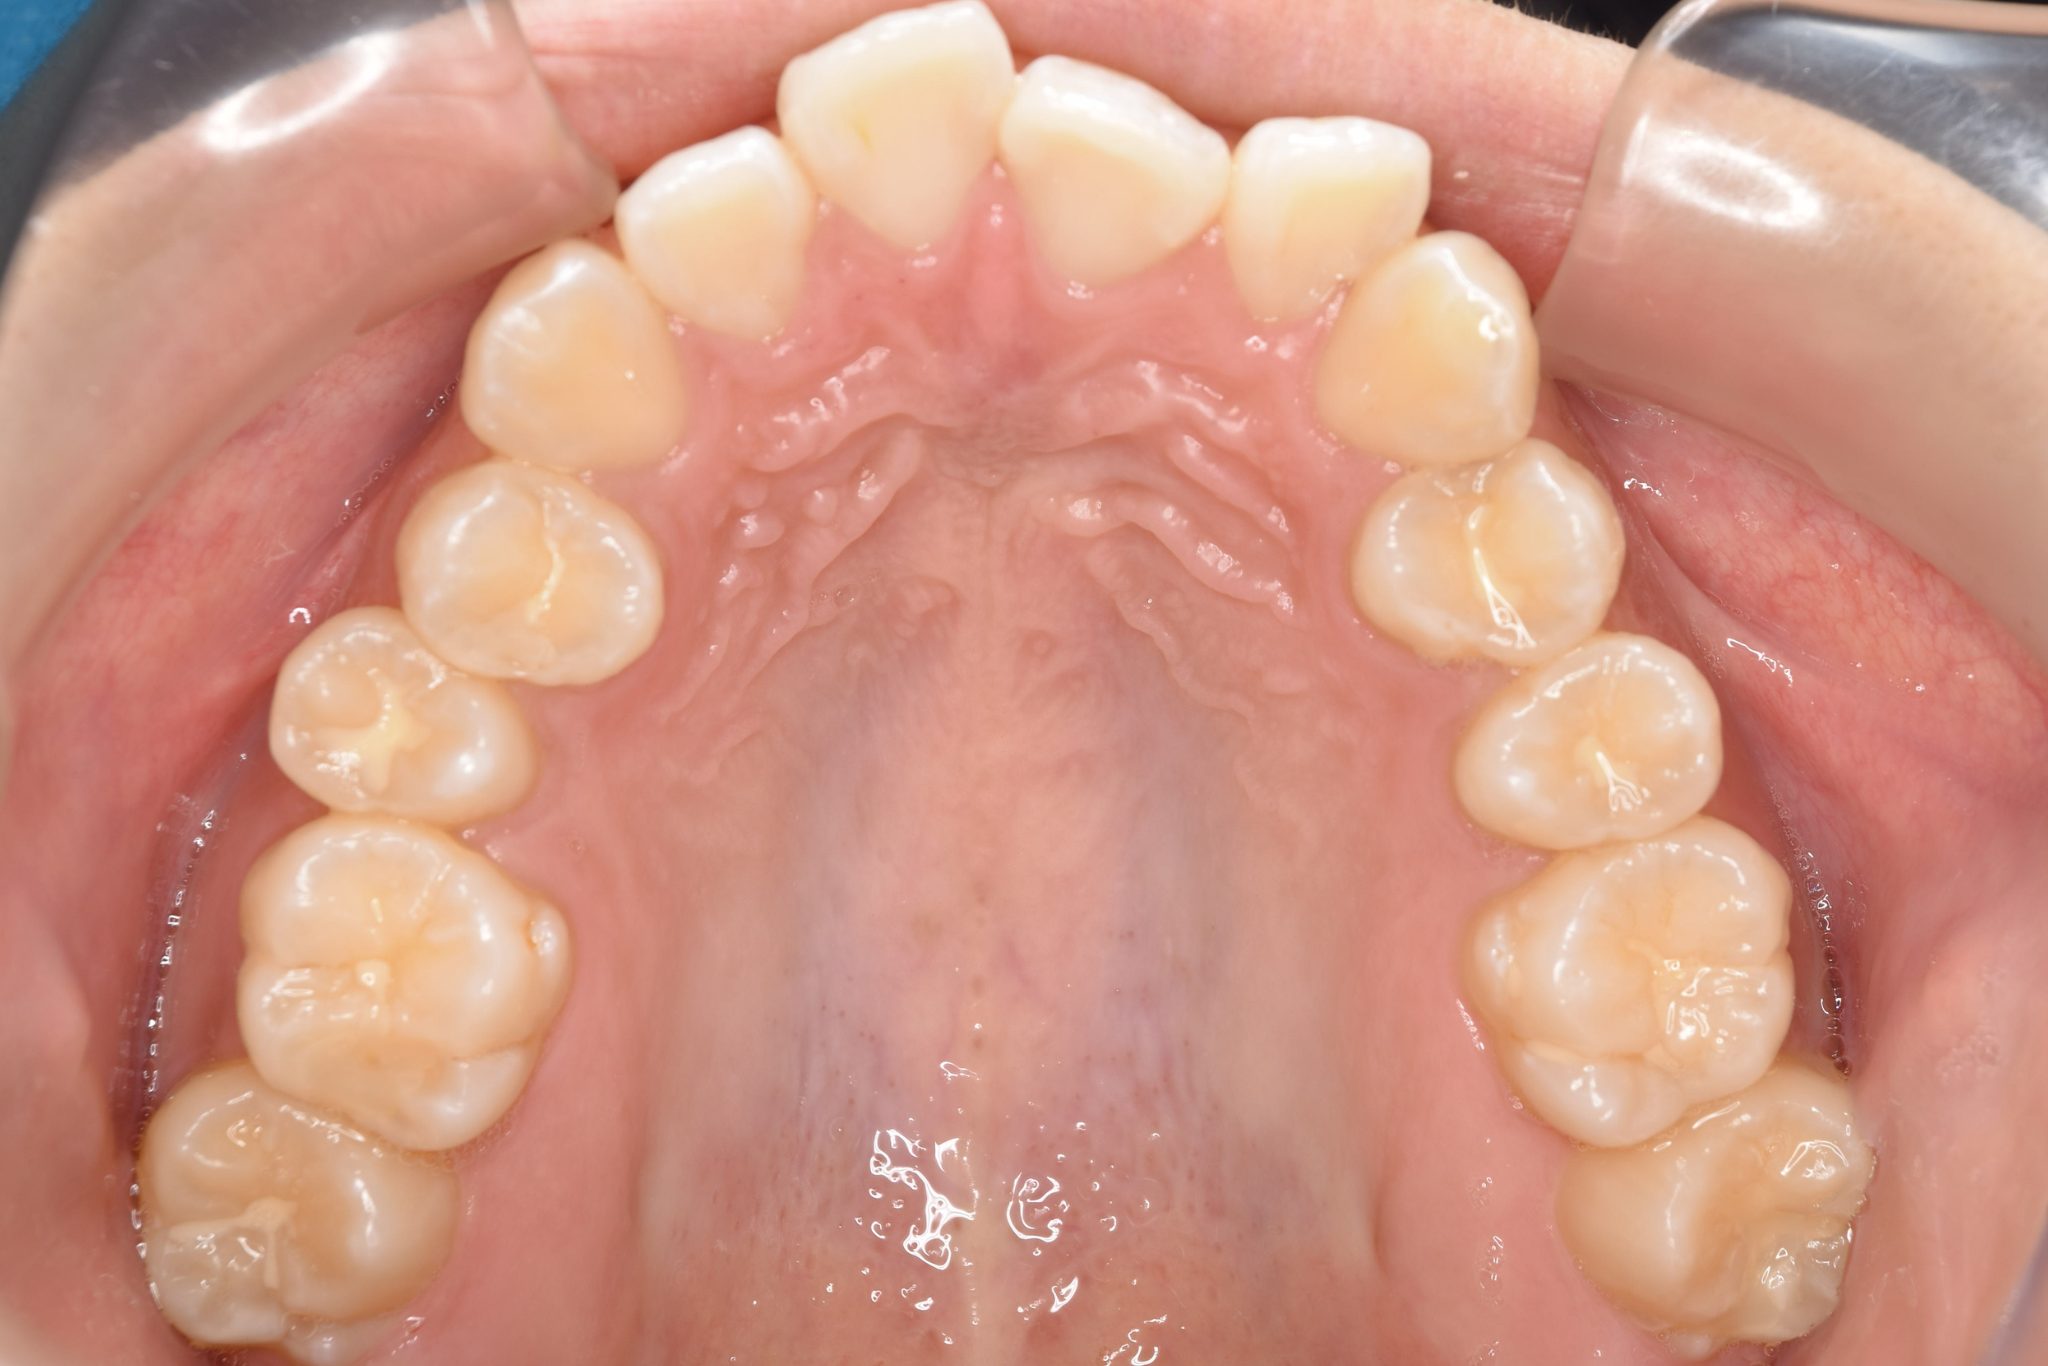

全顎ワイヤー矯正 症例_839